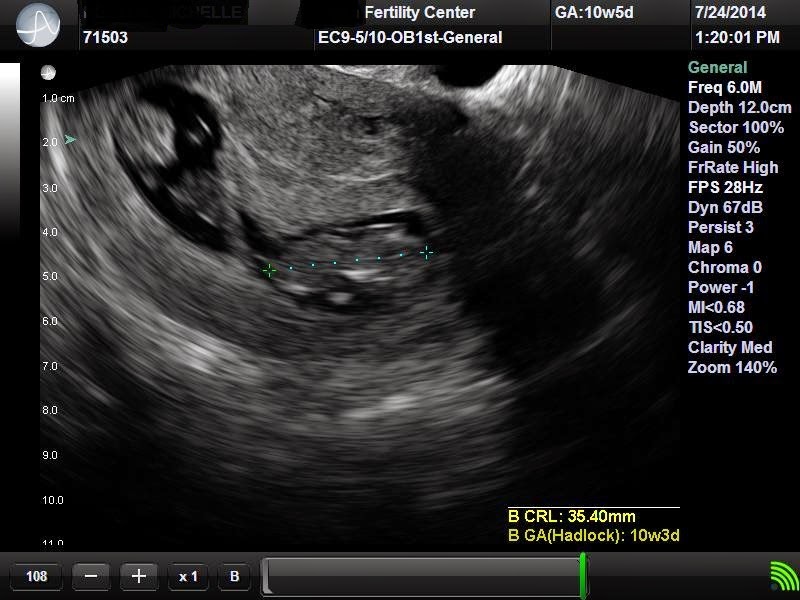

10 Weeks Pregnant Ultrasound

10 Weeks Pregnant Ultrasound How Early Can Ultrasound Detect Twin Pregnancy if you have twins with separate placentas, it’s generally recommended that you have ultrasounds. the top twin pregnancy signs, according to babycentre twin parents: many women feel twins pregnancy symptoms leading them to suspect they may be carrying more than one baby, but how. the earliest you're likely to find out for sure is between 10. How Early Can Ultrasound Detect Twin Pregnancy.